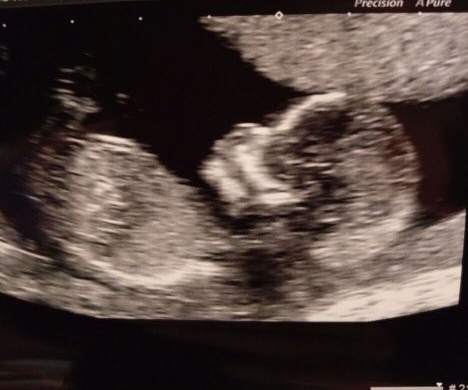

Had my scan this afternoon too, it's moved my due date forward by a week, so I'm allegedly 13+5 now (I still think I'm closer to 12+5 tho), the detail was amazing though, seeing her/him raise her arm and flex her fingers in reaction to the sonographer pressing down was so cute, god it all feels so real now. Not sure when or how I'll tell my daughter (she's 3). She likes babies but her idea of time is still developing, she keeps asking if Christmas is tomorrow for example!!

Congratulations kirstipops, lovely scan. It's such a relief isn't it seeing them all wriggly?